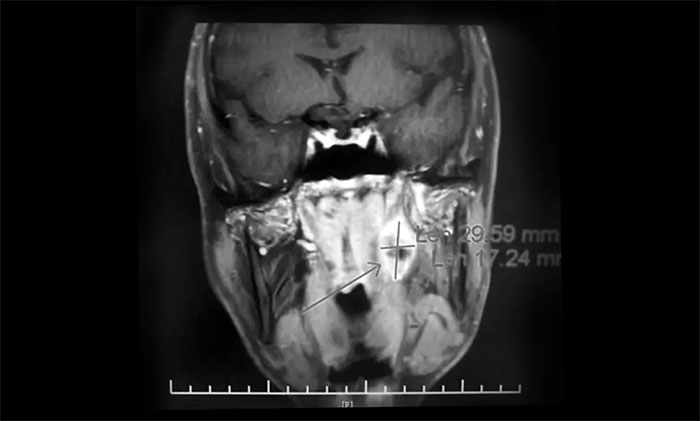

一位64歲男性患者,因“左頸部淋巴結(jié)腫大伴鼻出血半月”在外院行鼻咽鏡活檢病理結(jié)合影像學(xué)檢查,提示鼻咽癌可能。為尋求進(jìn)一步治療近期來到我院。查MRI:左側(cè)鼻咽部實(shí)性占位性病變,考慮惡性腫瘤,侵及左側(cè)咽旁間隙;左側(cè)下頜腺區(qū)及頸部淋巴結(jié)異常腫大(轉(zhuǎn)移可能)。

▲ 入院MRI影像